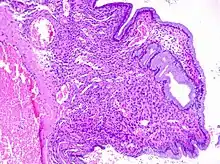

Cervical polyps can be seen during a pelvic examination as red or purple projections from the cervical canal.[4] Diagnosis can be confirmed by a cervical biopsy which will reveal the nature of the cells present.[4]

Cervical polyps are finger-like growths, generally less than 1 cm in diameter.[4][5] They are generally bright red in colour, with a spongy texture.[3] They may be attached to the cervix by a stalk (pedunculated) and occasionally prolapse into the vagina where they can be mistaken for endometrial polyps or submucosal fibroids.[5]